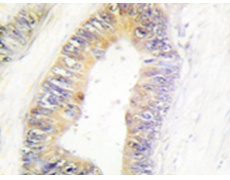

IHC positive control: |

Human colon carcinoma tissue |

IHC Recommend dilution: |

50-100 |